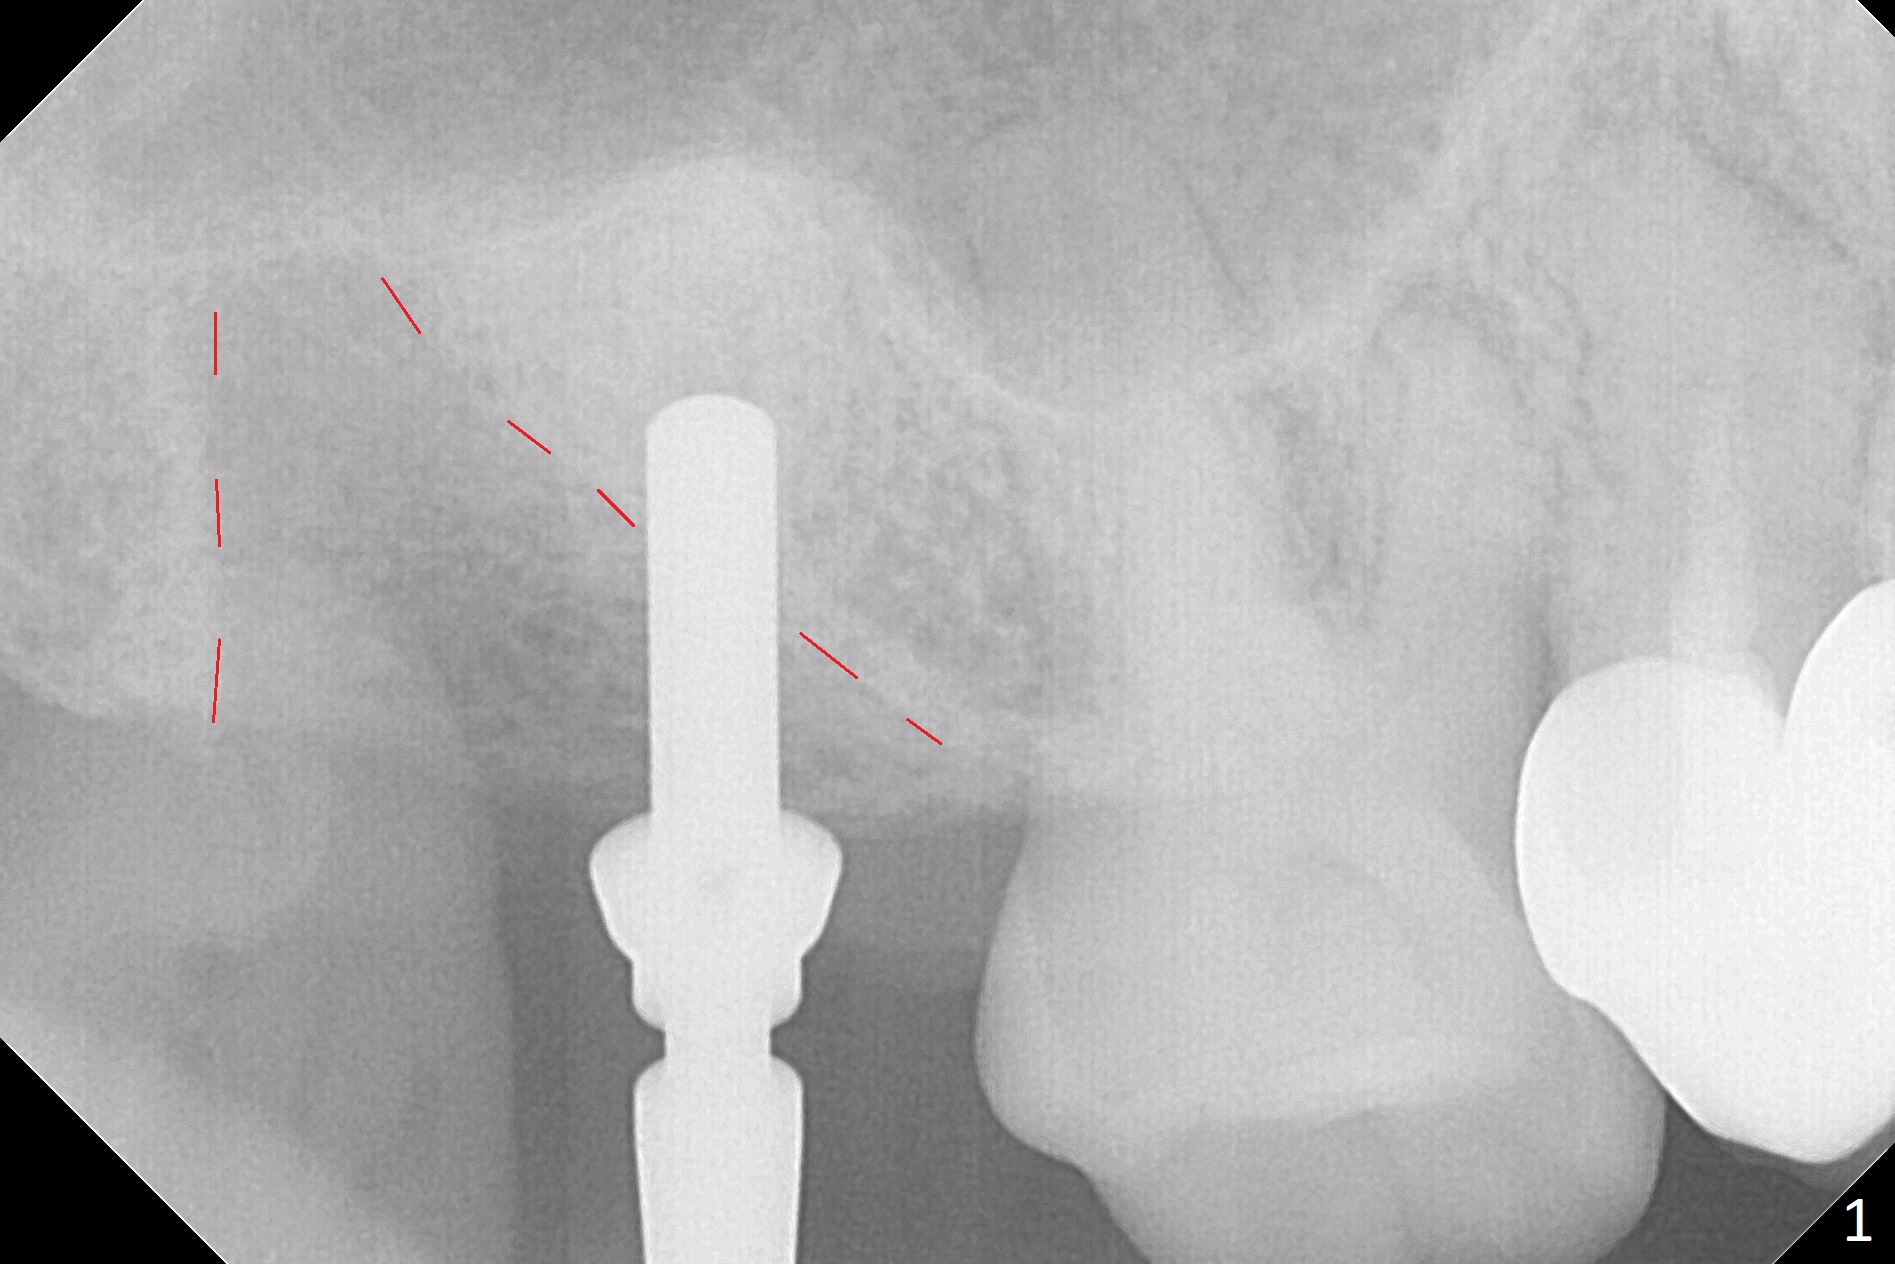

After extraction of the 3rd molar with mesial periodontal defect, osteotomy for 2nd molar implant is initiated in the mesial slope of the 3rd molar socket (Fig.1 red dashed line). When osteotomy is finished with IS drills and sinus lift with Magic Sinus Lifter (S-reamer with 11 mm stopper being short), a 4x10 mm dummy implant is placed with ~ 4 implant thread exposure (Fig.3). Following use of Lindamann bur to move osteotomy mesial and larger drill, a 4.5x10 mm implant is placed with 5-7 implant threads exposed distally (Fig.4,7 (~ 50 Ncm)). The bucco(B)-palatal(P) extent of the implant thread exposure is larger (Fig.5) than that associated with the 4 mm dummy implant (data not shown). The exposed implant surface is covered with Vera Graft (Fig.7*), Collagen plug and an immediate provisional after adjustment of abutment height (Fig.6,7). The bone density distal to the implant is low 3 months postop (Fig.8,9 CBCT) and 3.5 months postop (Fig.10,11). The permanent crown is cemented nearly 4 months postop. The distal cortical bone contacts the implant (Fig.12 ^), while the mesial bone increases in density (*) 2 years postop.